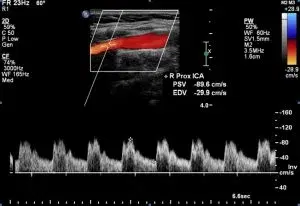

Carotid ultrasound involves using ultrasound imaging to diagnose carotid artery conditions. By analyzing grayscale, Doppler, and color images, diagnoses such as stenosis, atherosclerosis, fibromuscular dysplasia, carotid dissections, or carotid body tumors can be identified, aiding in treatment planning.

Describe spectral waveform changes associated with proximal and distal stenosis noted in carotid ultrasound exams.